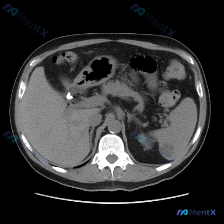

今天看到一个提问很有意思——直接问“脾脏病变”,但把影像资料和分析理了理,发现这里有个很典型的临床认知陷阱,整理出来和大家讨论。 先把完整客观影像信息放前面(别被提问带偏): --- 一、客观影像所见(腹部CT平扫软组织窗) 1. 图像质量:伪影少,软组织对比度好,满足诊断 2. 关键解剖结构: -...

整理了一份读片资料,这个病例一开始容易被「带偏」,先分享一下完整的影像信息和我的分析思路。 --- 影像基础信息 这是一张上腹部CT平扫横断面软组织窗图像,层面可看到肝、脾、胃及大血管,整体图像清晰度尚可。 关键影像表现 1. 肝脏:肝实质内可见多发散在、类圆形、边缘尚清晰的低密度灶,肝脏轮廓无明显...